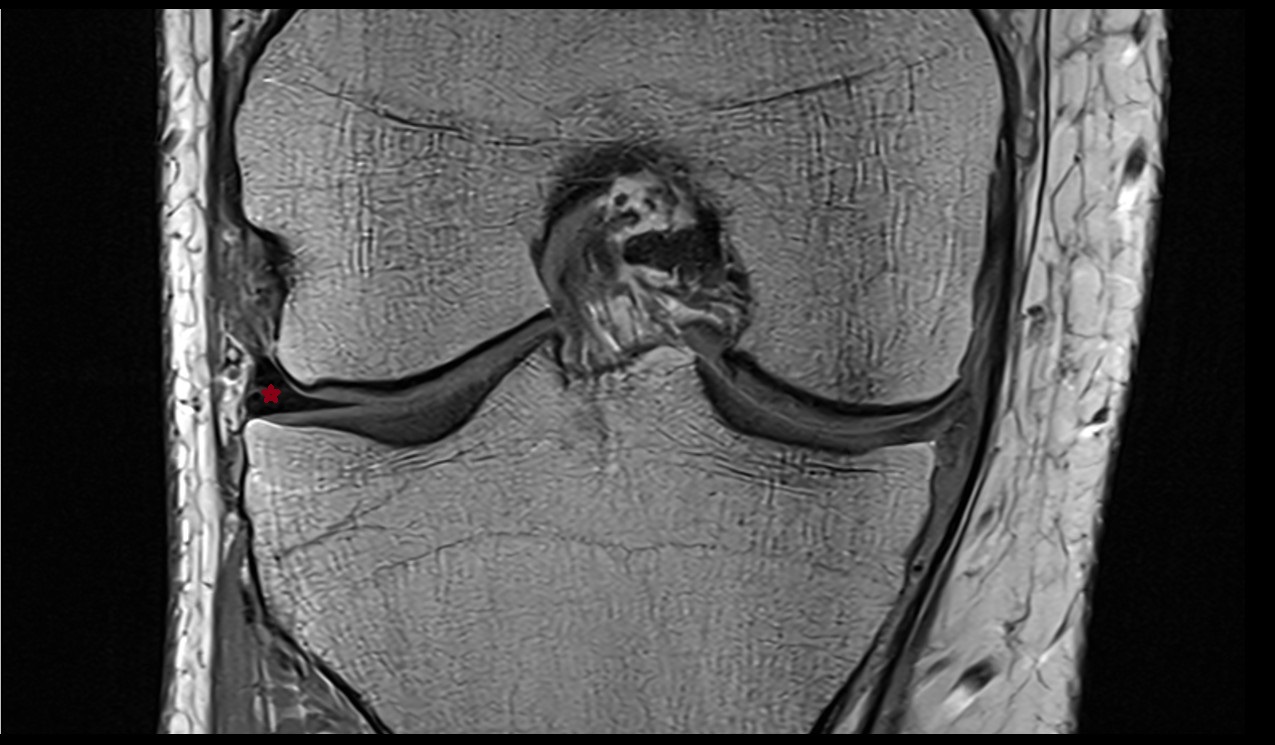

- Medial meniscus

- Lateral meniscus

- Anterior cruciate ligament

- Posterior cruciate ligament

- Knee Joint